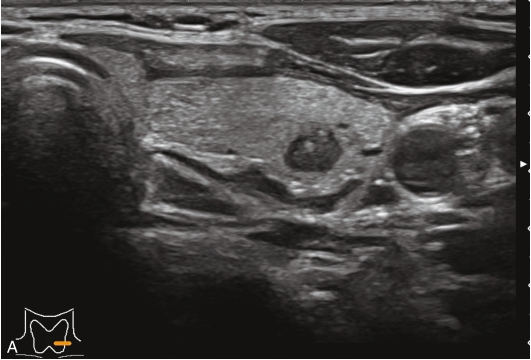

男性,52岁,外院发现甲状腺结节,为求进一步诊治收入我院。

甲状腺左叶中下部见一混合回声结节,边界清,形态规则,中心部可见斑状强回声,CDFI显示周边可见环状血流信号,其内可见丰富血流信号,见图1-3-18。

该结节早于周围腺体组织增强,结节内部呈高增强表现,可见部分无增强区;结节晚于周围腺体组织消退,仍呈高增强表现;结节周边可见均匀高增强环,甲状腺被膜未见明显中断,见图1-3-19、ER1-3-9。

(1)结节增强早期早于腺体增强或与腺体同步增强,增强晚期晚于腺体消退或与腺体同步消退。

(2)结节内部呈均匀或不均匀弥漫性等增强或高增强,增强水平通常高于周围腺体。

(3)结节与周围腺体分界清晰,形态较规则。

(4)部分结节周边可见均匀高增强环。

(5)结节周边被膜连续完整。

甲状腺滤泡性腺瘤通常为富血供病灶,其增强水平等于或高于周围腺体,并呈现“早增强,晚消退”的特点,重点需要与滤泡性腺癌鉴别,腺瘤多边界清晰、形态较规则,造影时结节周围的高增强环厚薄一致、较为均匀,结节周边被膜连续完整、无浸润表现,颈部淋巴结无异常肿大等。而滤泡性腺癌边界不清、呈浸润性生长表现,周边高增强环消失或厚薄不均,如发现颈部异常肿大淋巴结及被膜连续性中断等,需要高度警惕甲状腺恶性肿瘤。

图1-3-18 甲状腺滤泡性腺瘤常规超声声像图

A.甲状腺左叶纵切面超声图像;B.结节内部点状及斑状强回声;C.CDFI血流图